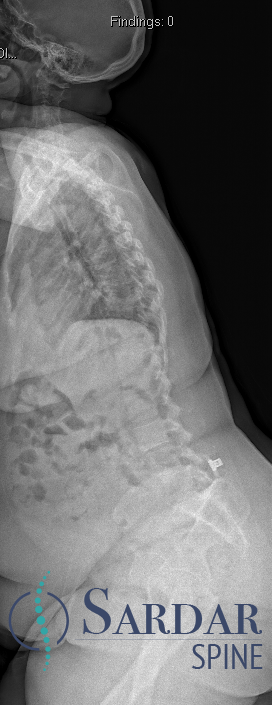

50s patient with severe malalignment. How would you treat this surgically? Nnee compensation in coronal and sagittal planes. Options: Multisegment instrumentation, TLIF/ALIF/OLIF, PSO, refer to another surgeon? Thoughts? #neurosurgery #spine #scoliosis #flatback #harringtonrods

Severe malalignment case: Performed T12-S1/Pelvis posterior instrumentation, TLIF at L5-S1 & L5 PSO. No anterior approach on vascular team's advice. Patient now stands upright & grateful. #SpineSurgery #MedTwitter #scoliosis #flatback #HarringtonRods #ScoliosisWarrior